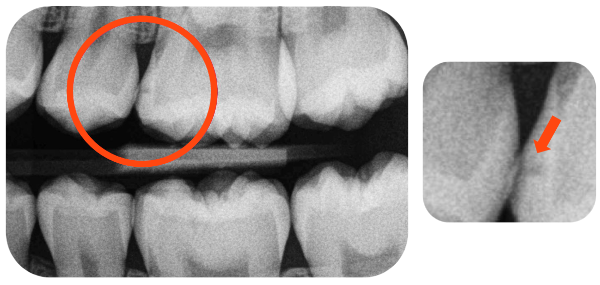

Before Curodont Application